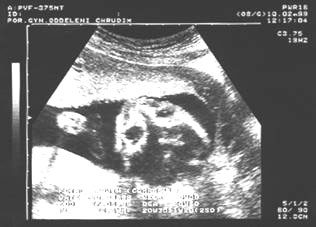

13. týden